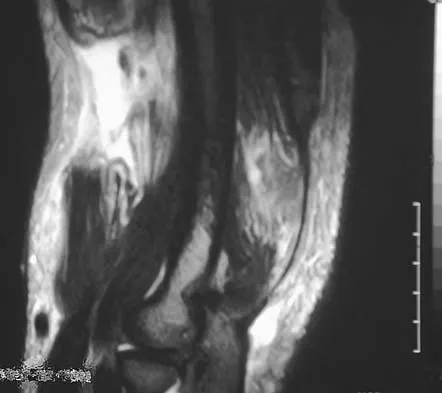

Question 50

A healthy, active, independent 74-year-old woman fell and sustained the elbow injury shown in Figures 41a and 41b. Management should consist of

Explanation